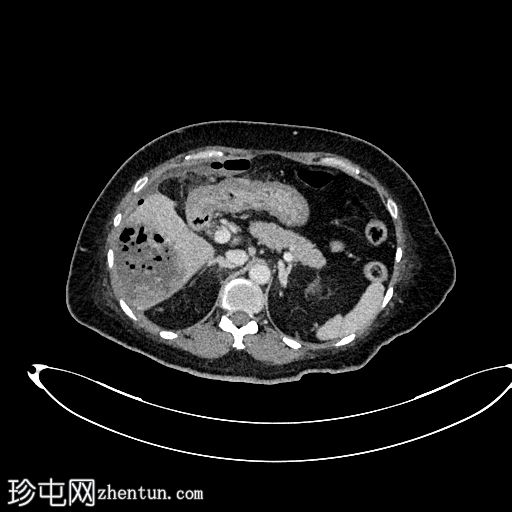

轴位增强(C+)

动脉期

5.jpg

轴位增强(C+)门静脉期

静脉期

6.jpg

肝段 6 和 7 可见多房性积液,呈环状强化

积液内可见多个气体腔

破入肝包膜下间隙,可见肝包膜下积液及气体腔

壁层腹膜与前腹壁之间可见另一局灶性积液

肝段 7 的肝内胆管局灶性扩张(0.3cm),内含气体腔

其他肝内胆管和肝外胆管均正常

胆囊缺失,可能由于既往胆囊切除术所致

无游离液体。

双侧肾皮质囊肿

轻度右侧胸腔积液伴邻近肺不张